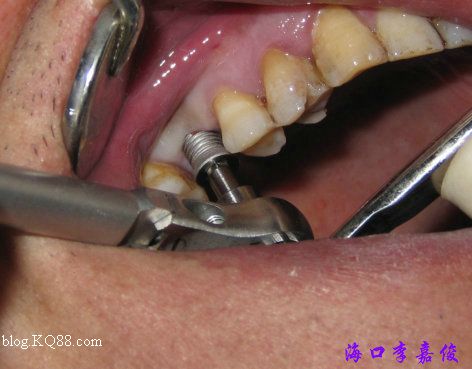

種植窩預備成形后植入4.8X10mm植體